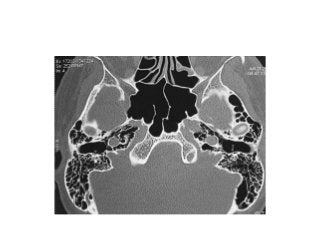

PETROUS APEX CHOLESTEATOMA - Dear surgeons today we did INFRA-COCHLEAR

approach to petrous apex cholesteatoma through BRACKS MANS TRIANGLE

cholesteatoma is completely removed with microscopic approach passing under the

vertical ica It was communicated intradurally Finally cavityis obliterared with fat Here